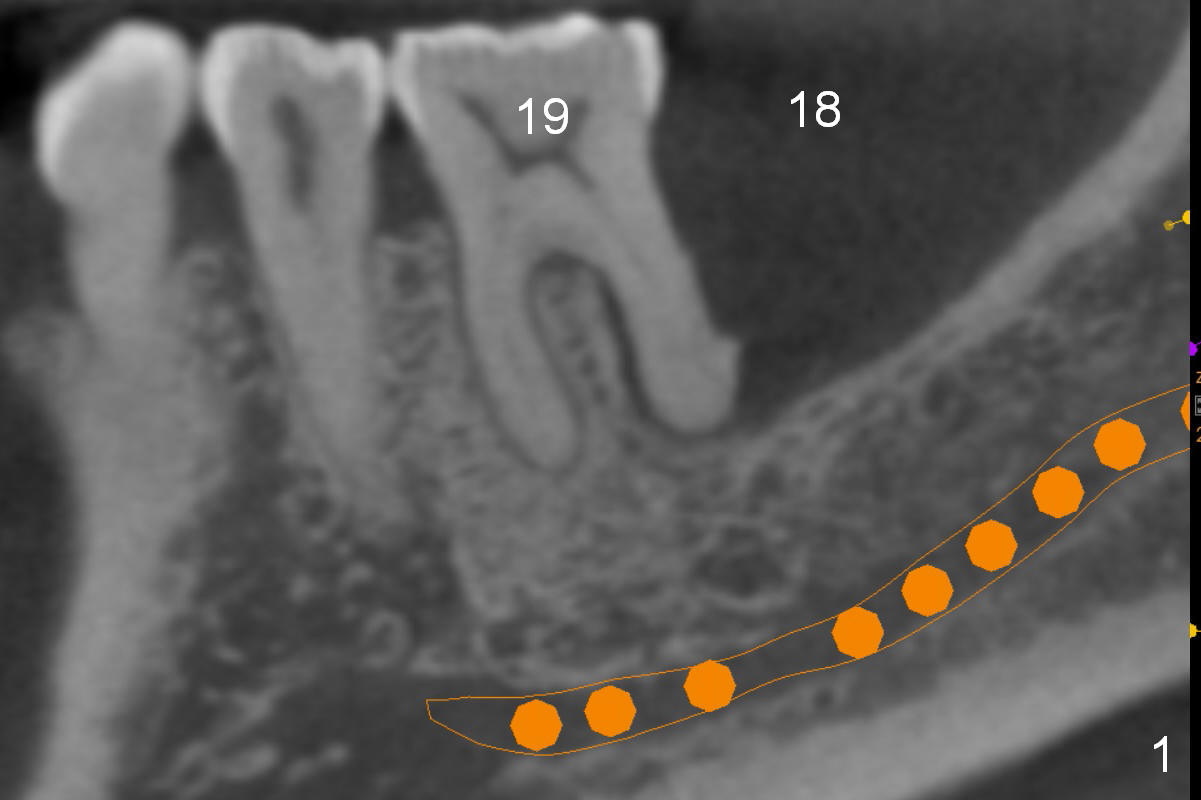

There is severe bone resorption around the distal root of the lower left 1st molar of the 56-year-old man (WG), while the loss of the 2nd molar is associated with limited bone height (Fig.1). A 5x14 mm implant will be placed at the mesial socket of #19 and 5.9 or 6.4x6 mm one is at the mesial site of #18 (Fig.7-9). Use a 2 mm pilot drill with 6 mm stopper from Sinus Master Kit (with extension) to initiate osteotomy at #18 immediately distal to the crown of #19, parallel to the long axis of the latter (Fig.2). After inserting a parallel pin at #18, extract the tooth #19 (Fig.3, antibiotic pending) and start osteotomy with a 2 mm pilot drill with 14 mm stopper (Fig.4). Insert the calibrated parallel pin at #19 (Fig.5) and measure the distance between the two parallel pins (approximately 10 mm, Fig.7). Sequential osteotomy and application of the Tatum taps (Fig.6 red rectangle) will push the septum distal (green arrow). As to #18 osteotomy, trephine, final and tap drills are to be used with control of the depth: 6 mm (Fig.7,9).